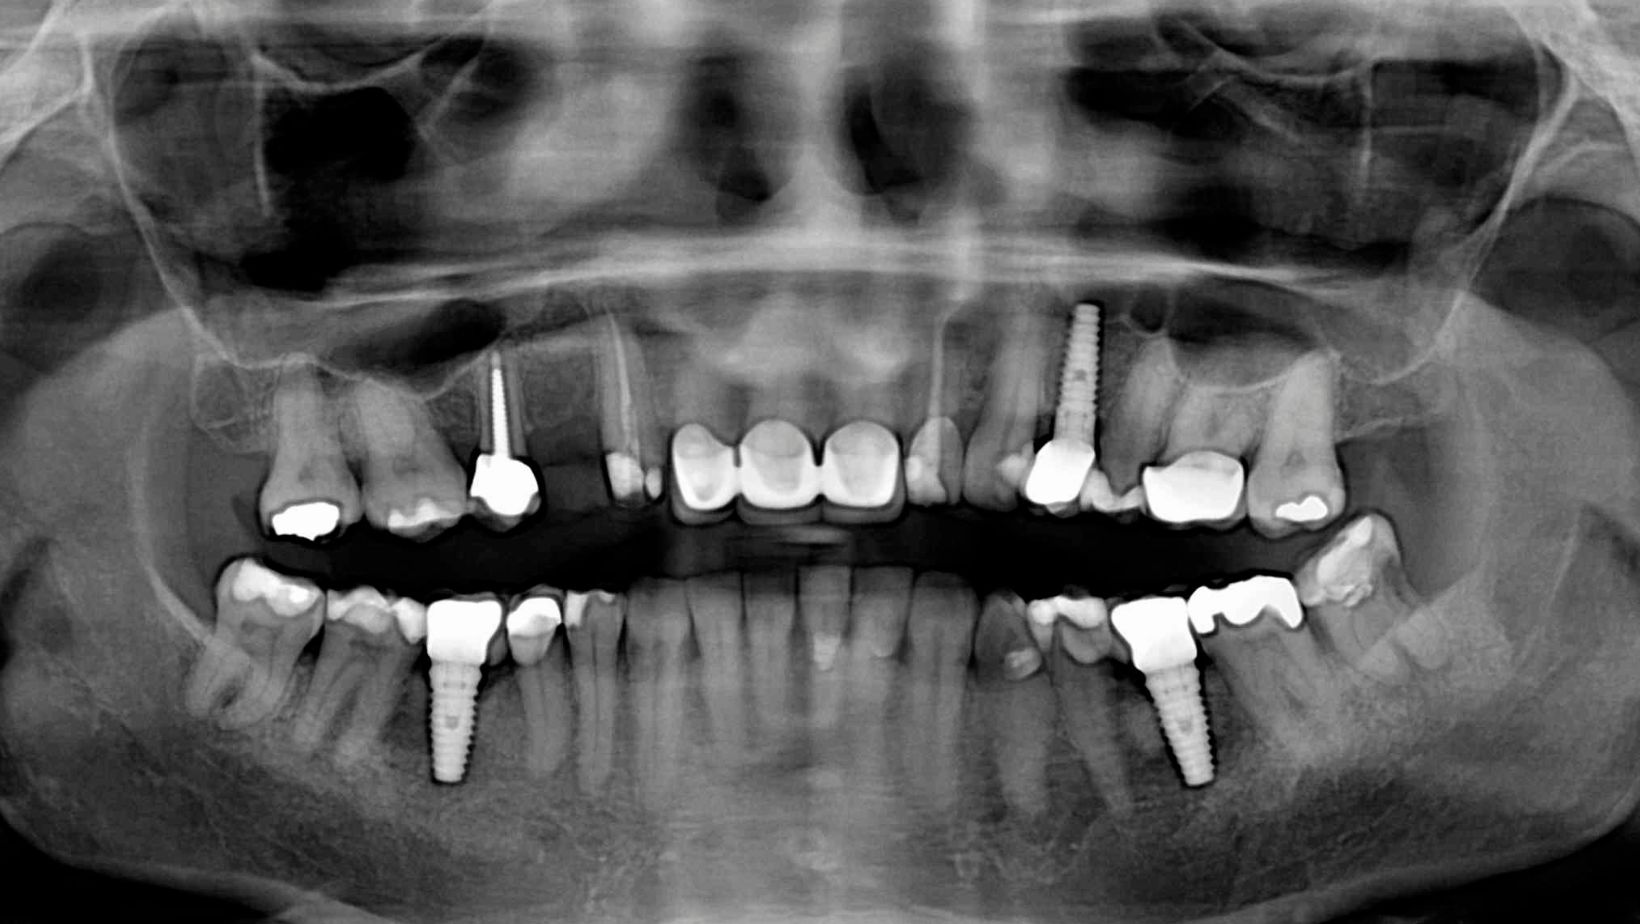

All-on-4 uses four implants to support a full-arch prosthesis. Two implants are placed near the front of the jaw straight up, and two are placed toward the back at an angle. The angled back implants let the surgeon use available bone and avoid anatomical structures like the sinus or nerve.

All-on-X takes the same full-arch idea but varies the implant count: All-on-4, All-on-5, All-on-6, or more, based on your jaw anatomy and clinical goals. The “X” lets your dentist choose the number and position of implants to improve stability, load distribution, and long-term support.

All-on-4 places two implants near the front of the jaw and two near the back that are often angled to avoid sinuses or weak bone. Angled posterior implants let your dentist use existing bone and often avoid grafting. That strategy shortens surgery and recovery for many patients.

All-on-X lets your clinician choose implant locations freely and may use tilted or vertical implants as needed. You can expect more planning time because the team will map your jaw with scans and place implants to match your bone volume and prosthetic needs. This approach can improve load distribution and long-term support when bone or shape is unusual.

All-on-4 uses exactly four implants per arch. Four implants are usually enough for a stable, fixed bridge when bone is adequate and well-placed implants are possible. Fewer implants can lower cost and shorten treatment, but might increase stress on each implant.

All-on-X allows any number of implants—commonly 4, 6, or more—based on your bone and bite forces. More implants spread chewing forces and can reduce strain on individual fixtures. Your clinician may recommend extra implants if you grind teeth, have low bone density, or want a stronger long-term solution.

You qualify for All-on-4 if you have moderate jaw bone volume and want fewer implants with a shorter treatment time. All-on-4 often uses two anterior vertical implants and two tilted posterior implants to avoid sinuses or nerves, so it suits many who wish to skip bone grafts.

All-on-X fits you if you have greater bone loss or want higher prosthetic support and redundancy. Adding implants (All-on-6 or more) gives more stability and backup if one implant fails, but it typically needs more surgery and higher cost.

Jaw bone quality and quantity directly affect implant placement and long-term success. Dense anterior bone often allows immediate loading with All-on-4, while thin posterior bone may require grafting or sinus lift if you want more posterior implants.

Tilted posterior implants in All-on-4 avoid anatomical limits but reduce the implant’s vertical bone contact. That works if you have good anterior bone and controlled bite forces. If your jaw shape or bone resorption is severe, adding implants (All-on-X) or doing bone augmentation may be safer.

Cone-beam CT scans guide decisions. Your clinician will measure bone height, width, and density and plan implant number, position, and angulation to minimize risk and maximize prosthetic support.